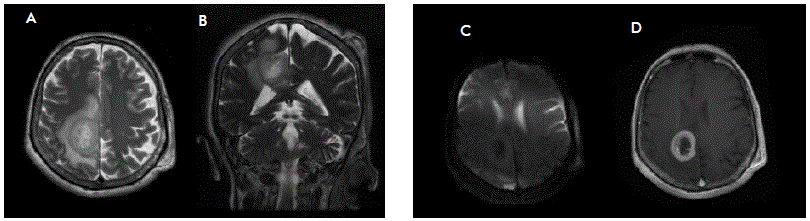

Magnetic resonance imaging (MRI) showed a left central lobe, heterogenous, gadolinium-enhanced mass with perilesional edema, 30 mm in diameter (Figure 1). 19-fdg pet scan provided additional information about activity exclusively in the CNS. Once identified, the mass was surgically resected by craniectomy with an interhemispheric approach and endoport- assisted surgical evacuation. We identified a highly vascular, round-shaped specimen intraoperatively with a yellowish appearance. There were no postoperative complications.

Figure 1 Magnetic resonance imaging. A-D Brain lesion identified during diagnostic assessment. Axial T2-weighted imaging (A) shows an intrinsic heterogeneously lesion located in the left central lobe, well delimited with significant perilesional edema. Contrast-enhanced T1-weighted imaging (D) demonstrates peripheral contrast uptake, with effacement of surrounding brain sulci. Coronal T2-DWI (B) shows no apparent restriction.